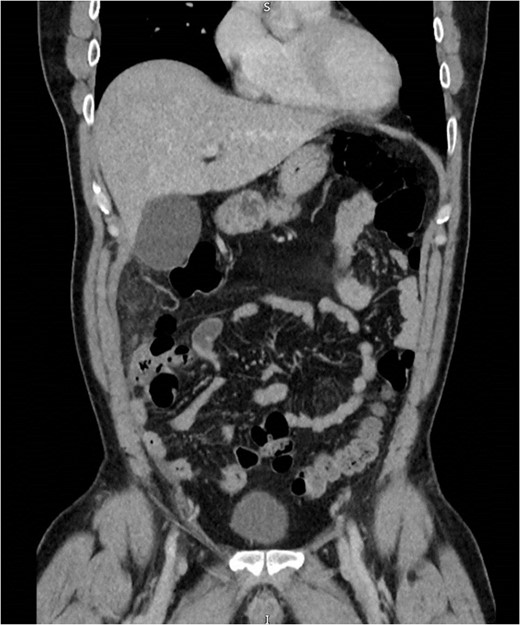

An initial differential diagnosis was made as cholecystitis. Appropriate intravenous antibiotics were commenced. An abdominal ultrasound demonstrated a thin-walled gallbladder without gallstones and a normal common bile duct caliber. There was however a trace of free fluid in the right iliac fossa. The sonographer was unable to identify a normal appendix. The following afternoon a CT scan of his abdomen and pelvis demonstrated fluid in the right iliac fossa as well as his rectovesicular pouch. The appendix was normal, but there was tissue stranding adjacent to the caecum and ascending colon to the tip of the liver (Figs 1 and 2).

Abdominal CT demonstrating soft tissue stranding anterio-lateral to the ascending colon/caecum without evidence of bowel wall thickening.

Abdominal CT demonstrating soft tissue stranding and odema inferior to a normal gallbladder, extending to the caecum.